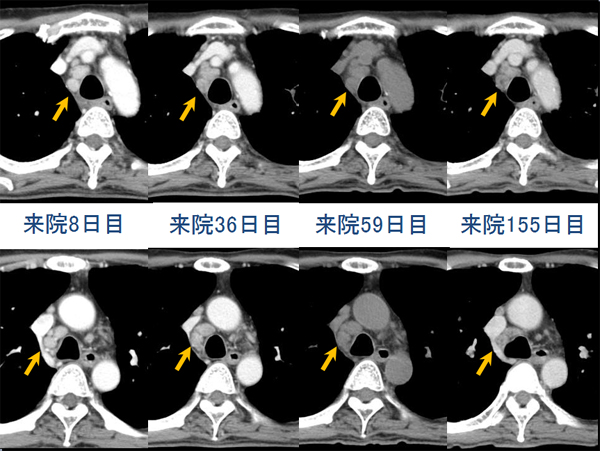

数日後という短時間で血液培養から抗酸菌が検出された→Rapidly growing mycobacterium (RGM)による敗血症と診断(図6)(図7)(図8)

遺伝子検査で最終的に Mycobacterium massiliense が同定された

抗菌薬(主にアミカシン)で加療され、肺病変は縮小

来院から約12か月後に骨髄異形性症候群の白血化により死亡